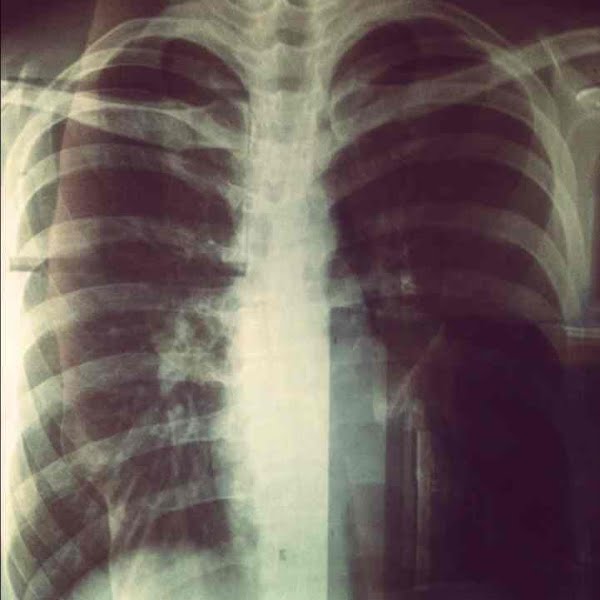

My X-Ray Film

Apparently my backbone arch to the right, meaning I'm no longer straight.